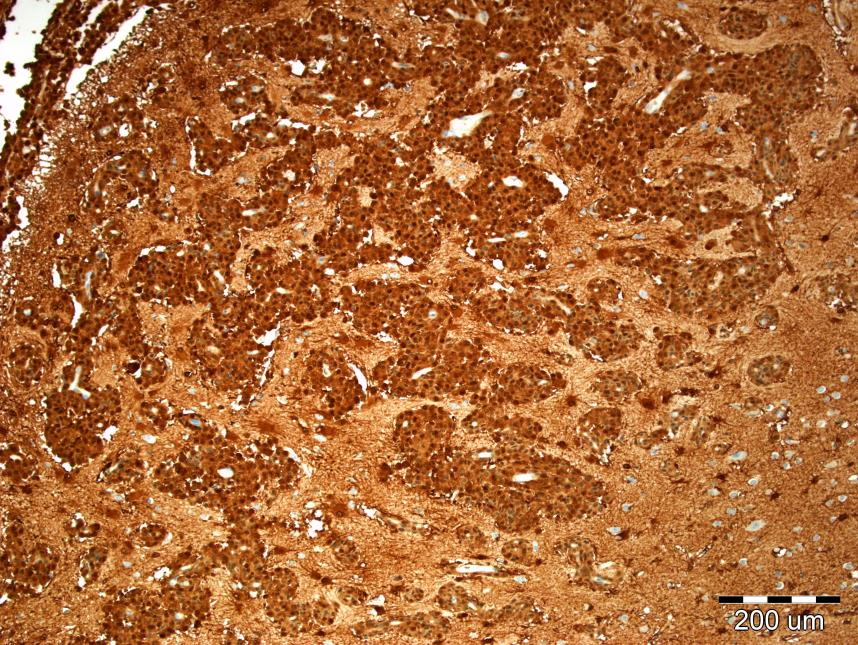

У багатьох випадках для підтвердження або уточнення діагнозу злоякісного новоутворення необхідне проведення імуногістохімічного дослідження гістологічних препаратів, суть якого полягає у виявленні специфічних білків пухлини за допомогою реакції антиген-антитіло. Таким чином можна діагностувати пухлини, встановлювати їх гістогенез, виявляти за структурою метастазу первинний пухлинний осередок, верифікувати передпухлинні процеси, прогнозувати перебіг онкологічного захворювання і, відповідно, обирати оптимальний варіант лікування, враховуючи можливу резистентність пухлинних клітин до променевої терапії та хімічних препаратів. У багатьох країнах метод імуногістохімічного дослідження біопсійного матеріалу не лише широко застосовується, але часто є обов’язковим елементом діагностичного процесу.

Рідкісний випадок менінгеального меланоматозу. Патологічний процес верифікований завдяки імуногістохімічному дослідженню – позитивна реакція з антитілом S100.

Стажування відбувалося у формі спільного діагностичного процесу разом з лікарями відділення патоморфології та подальшої дискусії і обговорення результатів. Враховуючи специфіку хірургічної роботи Вроцлавської університетської лікарні, основний обсяг біопсійного матеріалу складали пухлини шлунково-кишкового тракту, молочної залози, передміхурової залози, жіночих статевих органів, центральної нервової системи, нирок. Потрібно згадати про широке застосування пункційної біопсії печінки та нирок з метою встановлення клінічного діагнозу. При цьому імуногістохімічні методики використовуються не лише для виявлення пухлин, але й для верифікації інших патологій, зокрема різних форм гломерулопатій. В цілому застосовується більш, ніж 80 імуногістохімічних маркерів, переважно у різних комбінаціях, залежно від первинної оцінки характеру патології, яка дається на підставі гістологічної картини при банальних методиках забарвлення.